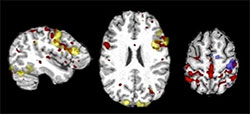

Figure 1: Language and motor networks from t-fMRI (yellow and blue) and rs-fMRI (red) in a patient with epilepsy.